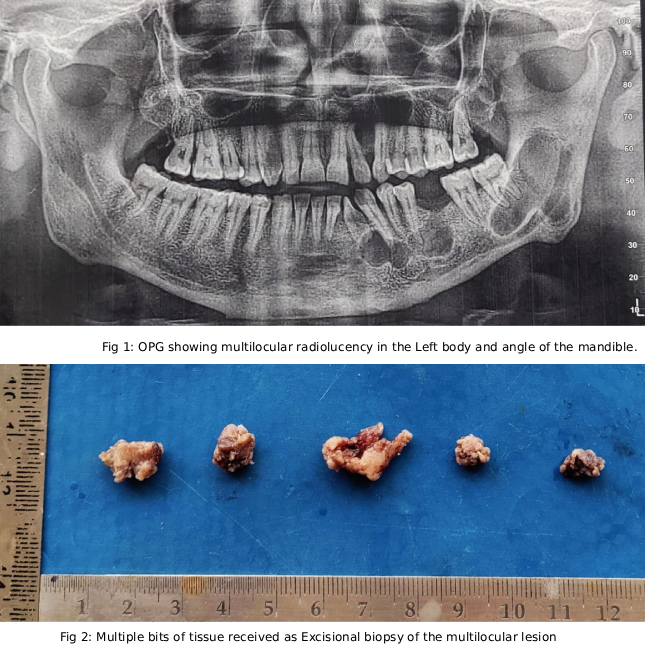

Case Study 4

Final Diagnosis: ODONTOGENIC KERATOCYST